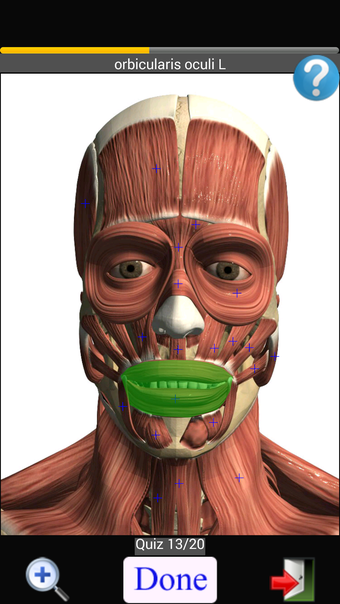

Anatomy Quiz Free es una aplicación de Android de Education Mobile que ofrece una amplia gama de cuestionarios para ayudar a los usuarios a aprender anatomía humana. La aplicación cuenta con más de 500 cuestionarios que ponen a prueba tu capacidad para identificar la ubicación correcta de un objeto dado su nombre. Los cuestionarios se generan a partir de modelos de anatomía 3D virtuales, lo que los hace más atractivos e interactivos. La aplicación es gratuita y no hay versiones premium ni compras dentro de la aplicación.

La aplicación es compatible con los idiomas inglés, francés, español y alemán, lo que la hace accesible para usuarios de diferentes partes del mundo. Las imágenes de alta resolución son nítidas y claras, y la función de zoom con pellizco te permite acercar y alejar las imágenes para una mejor vista. El cuestionario de posición viene con un temporizador, lo que lo hace más desafiante y emocionante. Además, la aplicación tiene una función de transferencia a la tarjeta SD, lo que facilita su transferencia a otros dispositivos.